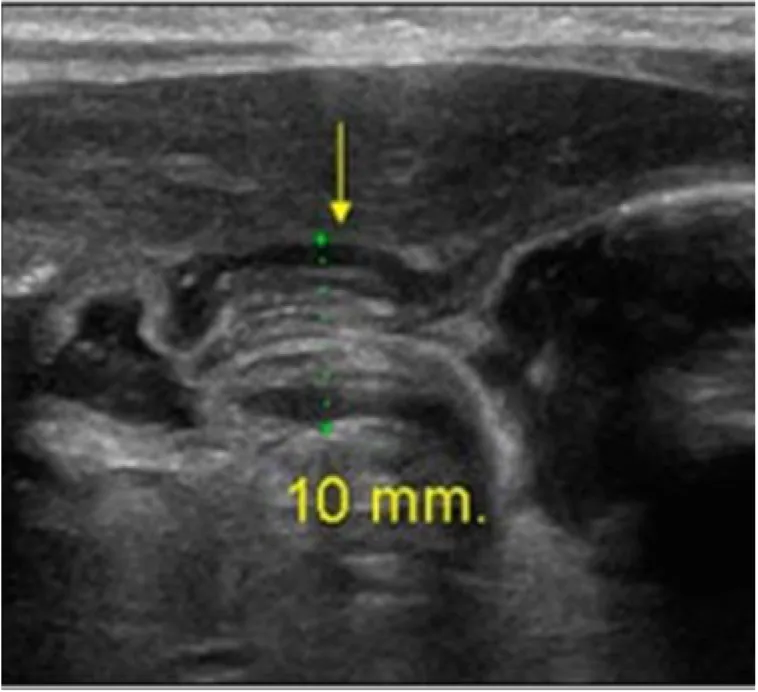

생후 4주된 남아가 식후에 자주 토하는 증상을 보인다고 어머니가 병원을 찾았다. 구토는 비담즙성으로 분출하는 양상을 보인다. 진찰 시 상복부에서 올리브와 유사한 크기의 덩어리가 촉지되었다. 혈액검사 결과와 복부 초음파 사진이다. 이 환자의 진단은 무엇인가?

• 생후 4주된 영아가 비담즙성 분출성 구토를 보이므로 비대 날문 협착증을 의심할 수 있다. 상복부의 올리브 크기 덩이가 촉지되는 것도 이를 뒷받침한다. 초음파 상 wall thickness가 증가(두께 ≥ 4mm)된 pylorus가 관찰되어 확진할 수 있다.